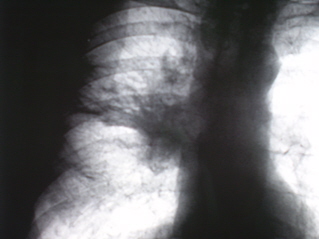

На рентгенограммах органов грудной полости, произведенных в стандартных проекциях – прямая и правая боковая (иллюстрации № 1 и № 2) определяется снижение прозрачности легочной ткани за счет инфильтрации в верхней доле правого лёгкого, с преимущественным поражением заднего и переднего сегментов. Также определяется снижение прозрачности легочной ткани в средней доле в виде очагов сливного характера с некоторым объёмным уменьшением. Плевра в главной и малой междолевых щелях плевра утолщена.